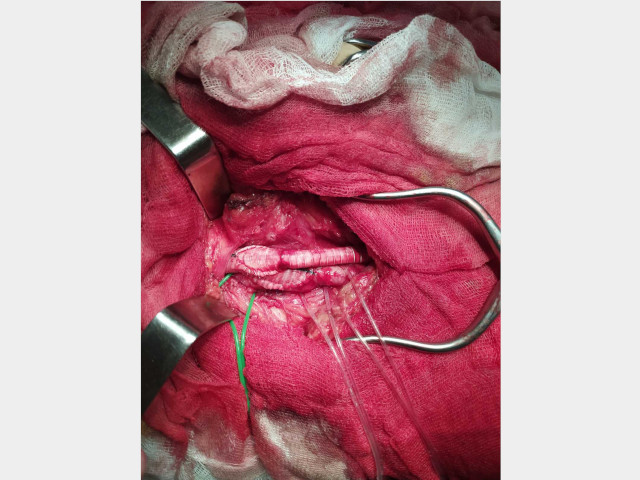

Пациент 2.

Диагноз: Мультифокальный атеросклероз. Стеноз 20% внутренней сонной артерии с обеих сторон. ХНМК 1. Окклюзия бедренно-подколенного сегмента слева. ХИНК II Б степени слева. (Операционная бригада: Лящук А.В., Нижельский В.Е.; Анестезиолог: Долженко С.В.).

03.03.2020 - производилась плановое оперативное лечение пациенту с окклюзией левой поверхностной бедренной артерии.

После операции у больного пульс на оперированной стопе нижней конечности.

Ассистент кафедры госпитальной хирургии и онкологии А.В.Лящук